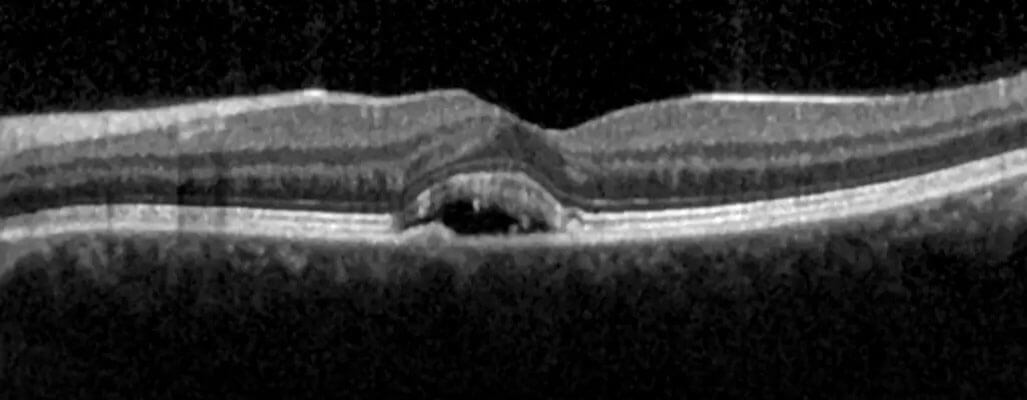

SSR hastalığına damlalı göz muayenesini takiben OCT (OKT, göz tomografisi) ile tanı konulmaktadır. Retinadaki sızıntı noktasının tayini için floresein anjiografi (FFA) ve koroiddeki sızdıran damarların tayini için indosyanin yeşil anjiografi (İSYA, ICG) tetkiklerini yapmak gerekmektedir.

OKT (OCT, göz tomografisi) konusunda ayrıntılı bilgiyi “Optik Koherens Tomografi (OCT) Nedir? Göz Tomografisi Nasıl Çekilir?” yazımda bulabilirsiniz. Floresein Anjiografi (Göz Anjiyosu) konusunda daha fazla bilgi isterseniz de “Fundus Floresein Anjiografi (FFA) Nedir? Göz Anjiyosu Nasıl Yapılmaktadır?” yazıma bakabilirsiniz.